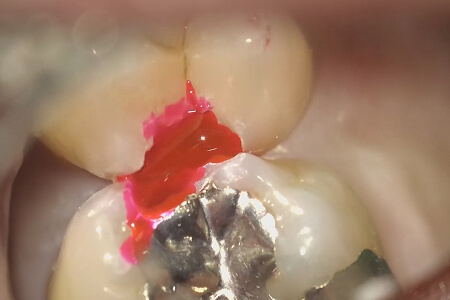

2つの歯の間に虫歯がみえる。

虫歯を取ったあと、虫歯を染めて虫歯が残ってないか確認する。

上の歯に少しピンクに染まる虫歯の部分がマイクロスコープで確認できる。